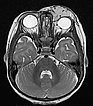

T2-gewichtete axiale MRT mit Fettsättigung. Die Raumforderung medial am linken Auge ist relativ homogen hyperintens und scharf abgrenzbar zum umgebenden Rand. Als Zeichen der starken arteriellen Durchblutung sieht man einige schwarze, signallose arterielle Gefäße in der Läsion („flow voids“). Auch dies ist typisch für ein infantiles Hämangiom.

T2-gewichtete axiale MRT ohne Fettsättigung. Die Raumforderung medial am linken Auge ist auch hier relativ homogen hyperintens und zeigt zentrale flow-voids. Aufgrund der fehlenden Fettsättigung ist die Raumforderung aber nicht so gut vom umgebenden Fettgewebe abgrenzbar.